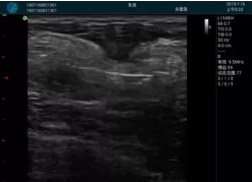

M20實(shí)時(shí)引導(dǎo):向包塊后方間隙注射利多卡因

清晰顯示腺體內(nèi)低回聲快影,邊界清晰,包膜較光滑

確定進(jìn)針路徑并實(shí)時(shí)監(jiān)測(cè)抽吸針與腫塊位置關(guān)系

抽吸針進(jìn)入腫塊內(nèi)部進(jìn)行旋切

抽吸過程中可見腫塊明顯縮小,并根據(jù)腫塊位置改變針道位置

抽吸旋切后再進(jìn)行超聲復(fù)查,原腫塊區(qū)域未見殘留組織及出血